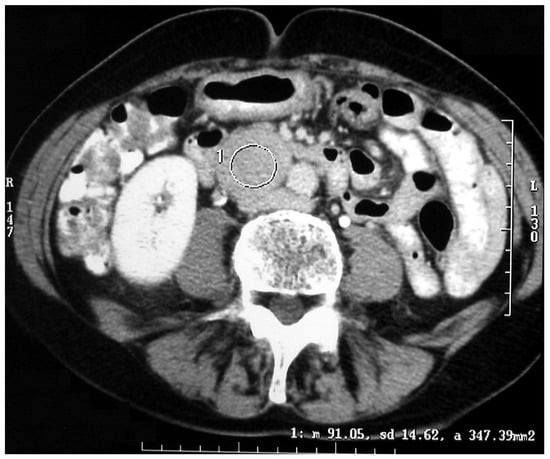

The diagnostic localization of a PCC/PGL is traditionally attempted only once excess catecholamine has been biochemically ascertained [17,18]. Both computed tomography (CT) scanning and MRI are mainstays for adrenal imaging and are used as the primary tests for localizing catecholamine-secreting tumors. CT is the preferred method for its excellent resolution (Figure 3 and Figure 4).

Figure 3. CT scan of an abdominal paraganglioma of above the aortic bifurcation (Zuckerkandl organ’s).

Figure 4. Pathological specimen of the abdominal paraganglioma reported in Figure 3.